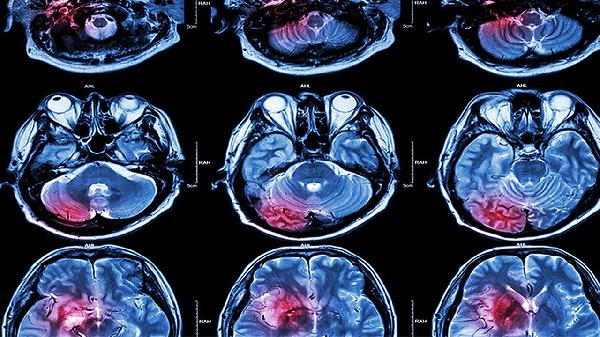

左后脑勺一阵一阵的痛可能由紧张性头痛、偏头痛、颈椎病、枕神经痛、高血压等原因引起,可通过热敷按摩、药物治疗、物理治疗等方式缓解。建议及时就医明确病因。